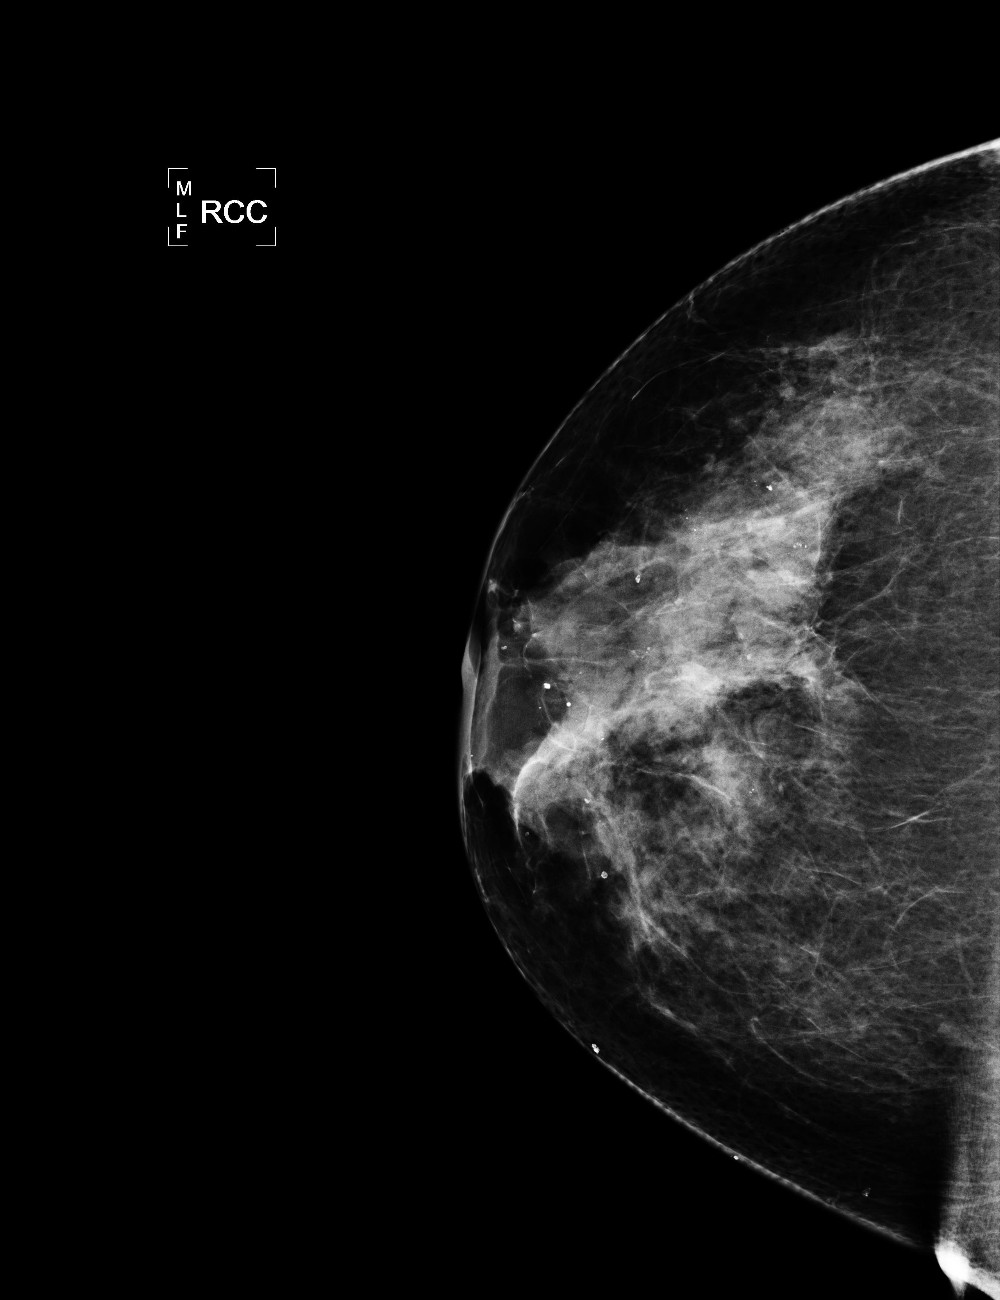

Ca sa intelegem cum si la ce foloseste, iata mai intai cum arata o mamografie normala, facuta cu tehnica medicala obisnuita:

Iar acum priviti imaginea aceluiasi san, post-procesata prin intermediul algoritmului de la NASA Goddard Space Flight Center.

Uneltele de analiza coloreaza artificial fotografiile alb-negru, pentru ca ajuta doctorii sa vada tumorile mult mai repede.